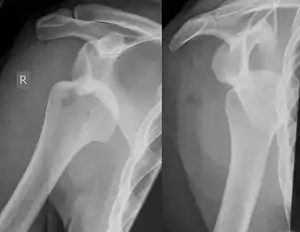

Hill–Sachs lesion post-shoulder dislocation

X-ray at left shows anterior dislocation in a young man after trying to get up from his bed. X-ray at right shows same shoulder after reduction and internal rotation, revealing both a Bankart lesion and a Hill-Sachs lesion.